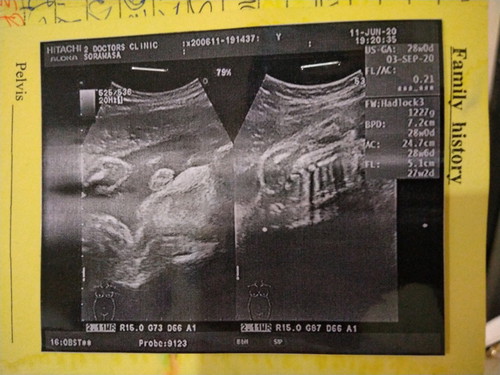

แบบนี้ ผญ หรือ ผญ คะคุณลุงหมอแอบไม่มั่นใจน้องให้เห็นไม่ชัด แม่28w แล้ว ❤️